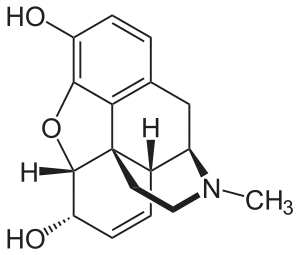

In the 19th century, two major scientific advances were made that had far-reaching effects. Around 1804, German pharmacist Friedrich Sertürner isolated morphine from opium. He described its crystallization, structure, and pharmacological properties in a well-received paper in 1817.[211][213][208][214] Morphine was the first alkaloid to be isolated from any medicinal plant, the beginning of modern scientific drug discovery.[211][215]

Several semi-synthetic opioids were developed in Germany in the 1910s. The first, oxymorphone, was synthesized from thebaine, an opioid alkaloid in opium poppies, in 1914.[228] Next, Martin Freund and Edmund Speyer developed oxycodone, also from thebaine, at the University of Frankfurt in 1916.[229] In 1920, hydrocodone was prepared by Carl Mannich and Helene Löwenheim, deriving it from codeine. In 1924, hydromorphone was synthesized by adding hydrogen to morphine. Etorphine was synthesized in 1960, from the oripavine in opium poppy straw. Buprenorphine was discovered in 1972.[228]